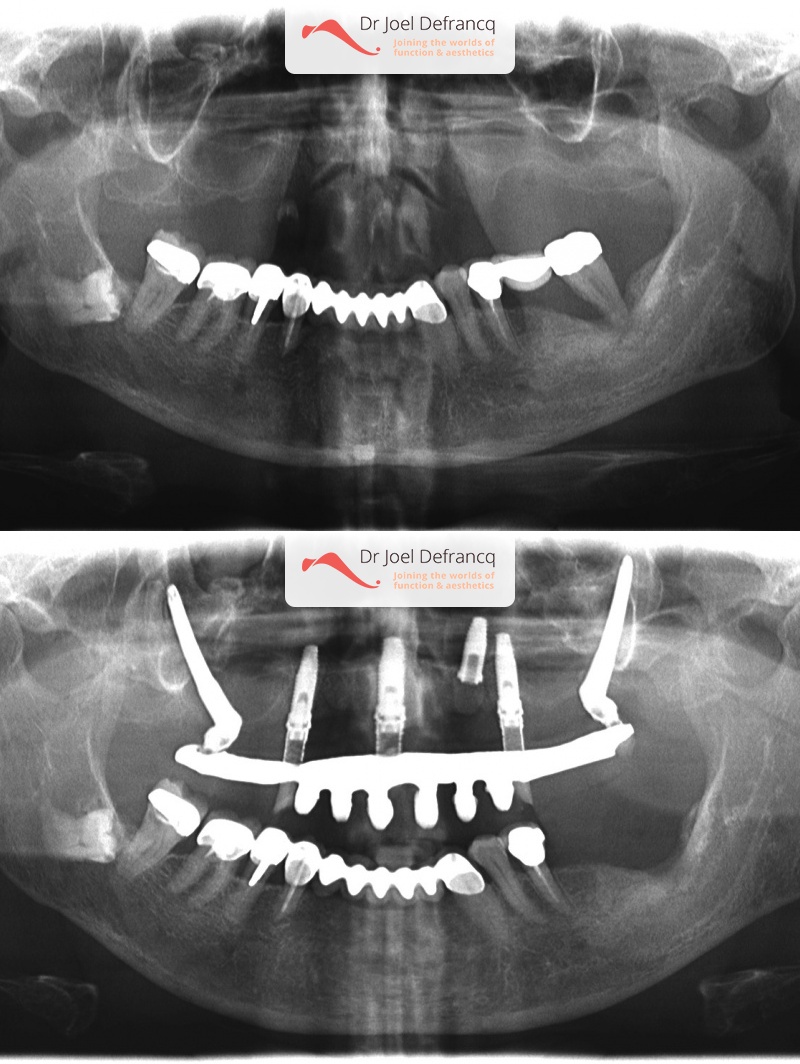

Raymonde

Dentale diagnose

- Open beet

Behandeling tandheelkundige implantaten

- Vaste tanden op implantaten (bovenkaak)

- Zygoma implantaten